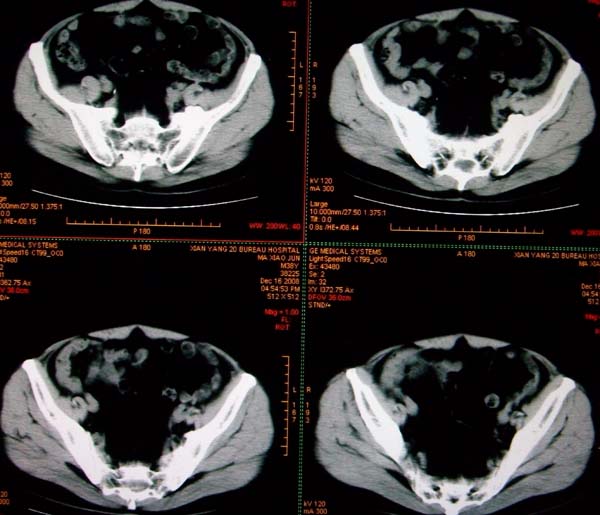

标题: CT17174:M38Y,体检超声提示右肾发育不良,病人无明显不适 [打印本页]

标题: CT17174:M38Y,体检超声提示右肾发育不良,病人无明显不适

右肾发育不良;考虑左肾下极血管平滑肌脂肪瘤可能,建议增强。

1)左肾下极占位性病变,不排除肾癌可能;建议行进一步检查。2)右肾发育不良。

左肾下极占位性病变,不排除肾癌可能;建议增强及明确内部组织ct值。右肾发育不良。

右肾发育不良。左肾代偿。左肾下极占位,性质待定,建议强化。

右肾发育不良。左肾下极囊实性占位,建议增强。